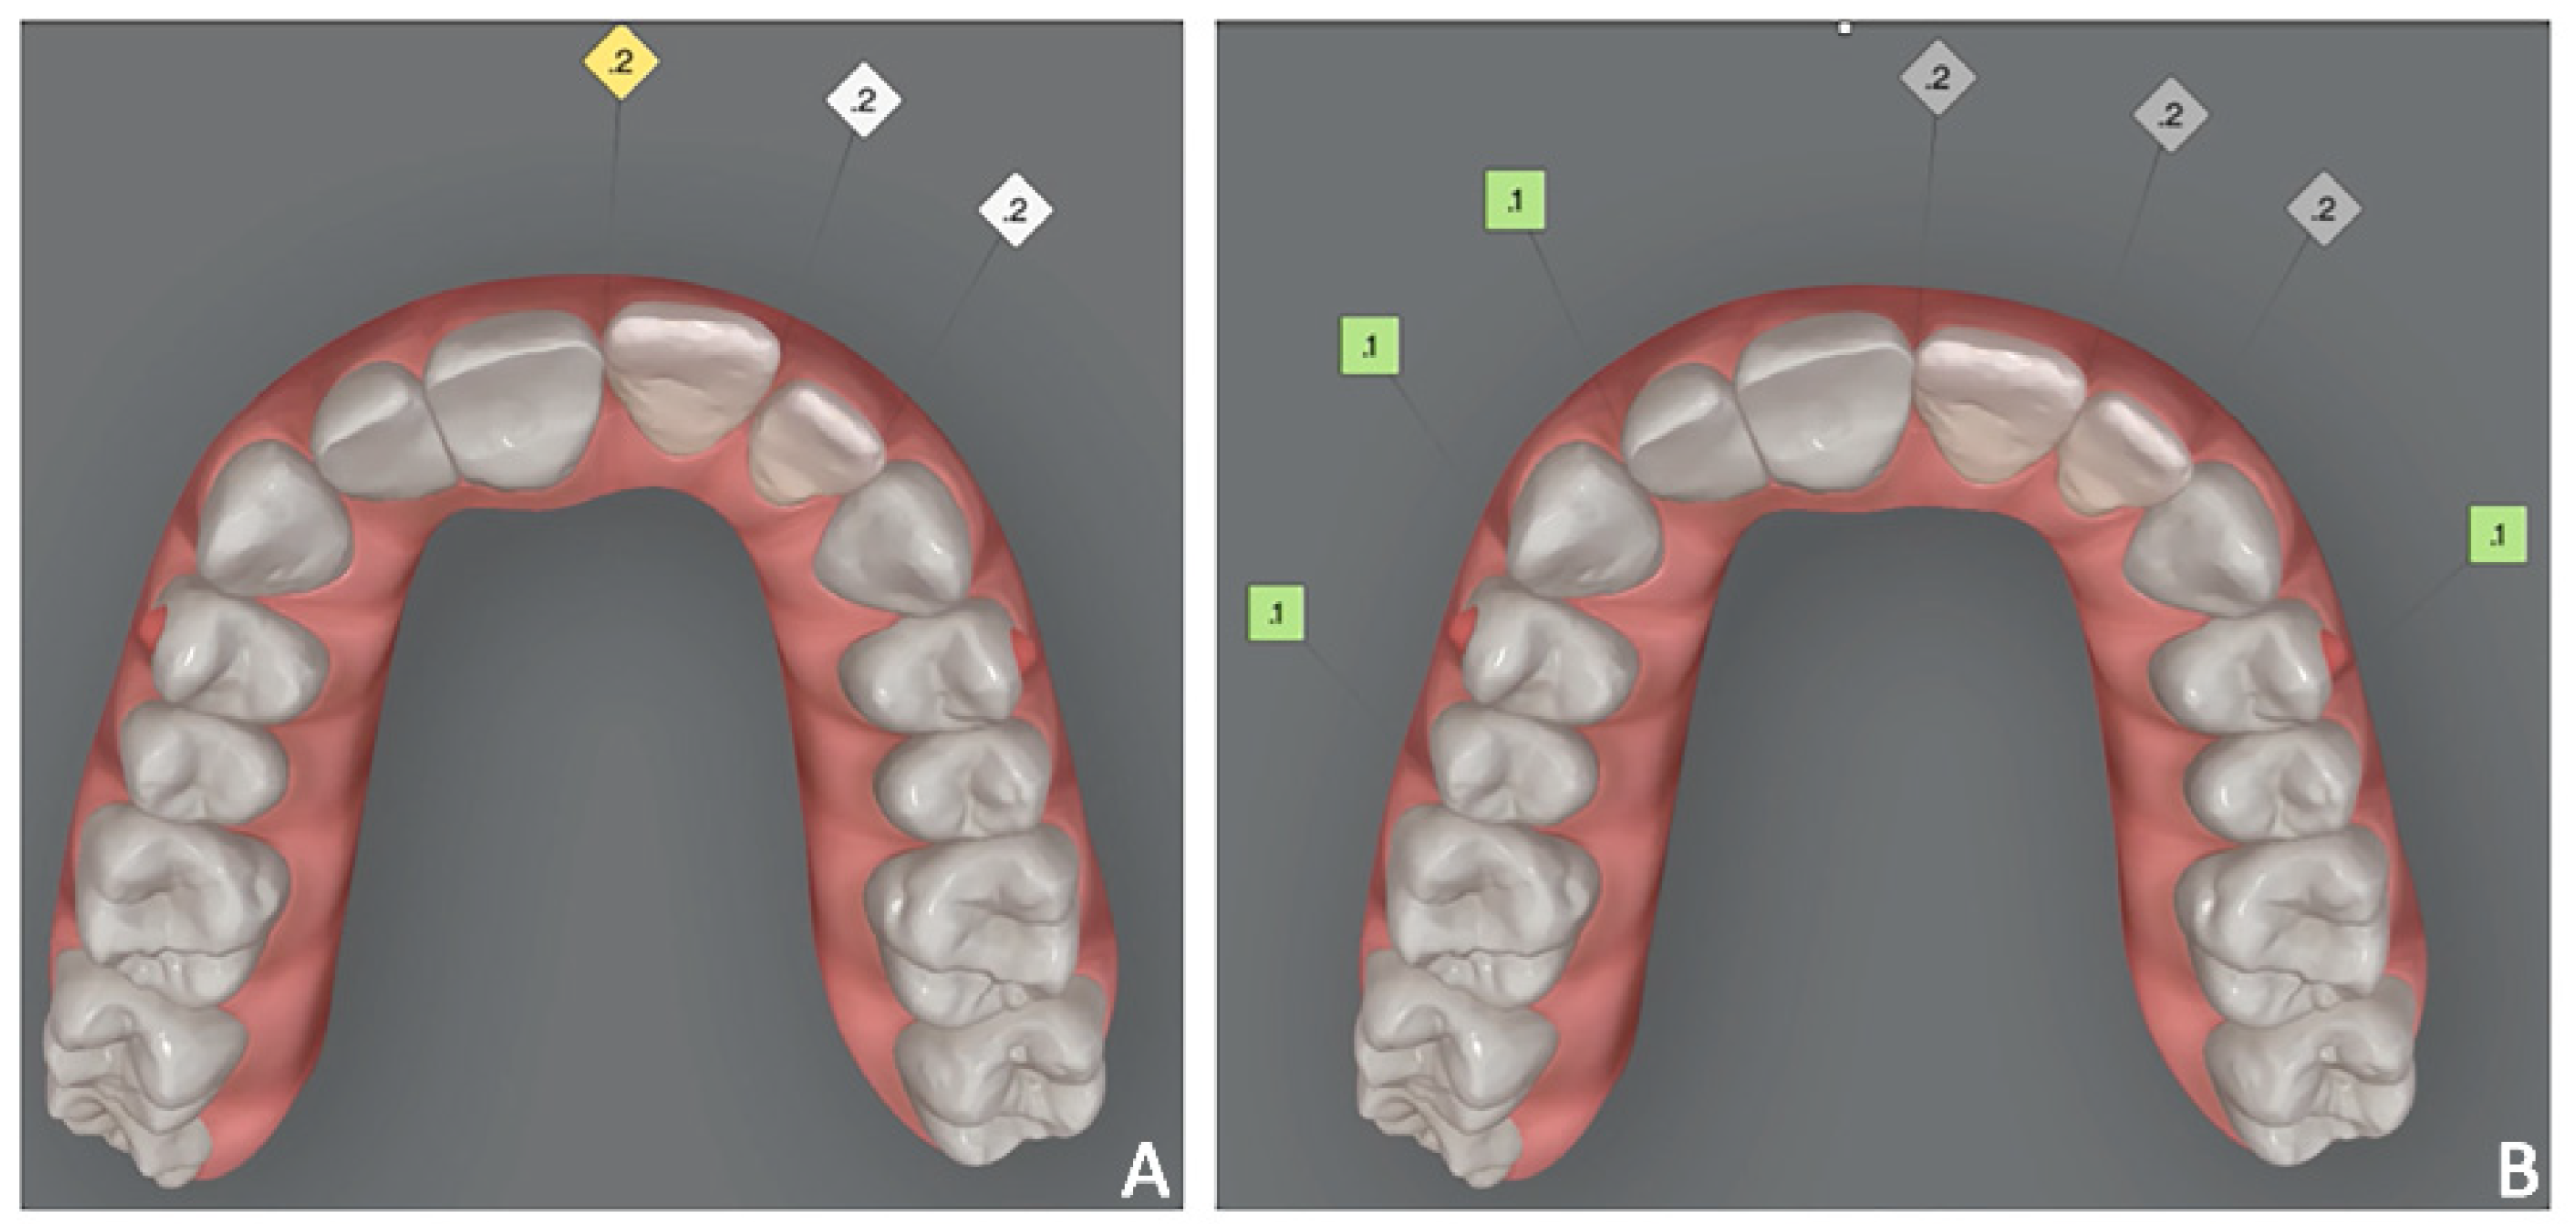

Figure 3. Case 1. Orthodontic set-up for staging movement for clear aligners therapy (Invisalign Go). (A) Pre-staged occlusal view; (B) post-staged occlusal view; (C) post-staged frontal view.

Orthodontic set-up. The Clincheck software (Invisalign GO) was used for evaluating dental occlusion and planning pre-prosthetic tooth movements (Figure 3). Afterward, the file of the final dental position was exported from the Invisalign GO digital platform. This file allows the dental technician to optimize the design of the veneers with reference to the final dental positions.